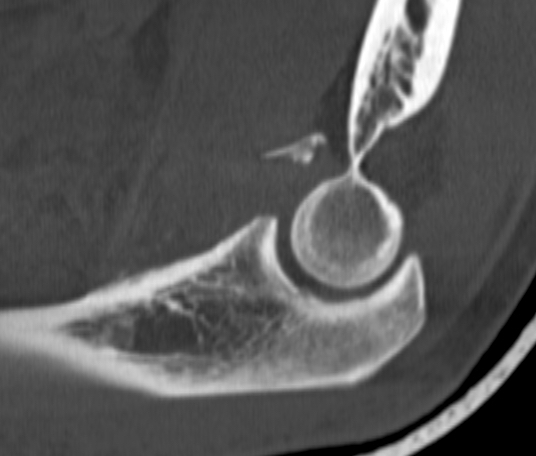

mason 1 CT Radial Head Fracture Type 3 radial head

Comminuted fracture radial head

Unreconstructable

Radial head replacement

+ LCL repair / reconstruction

+/- MCL repair / reconstruction if unstable